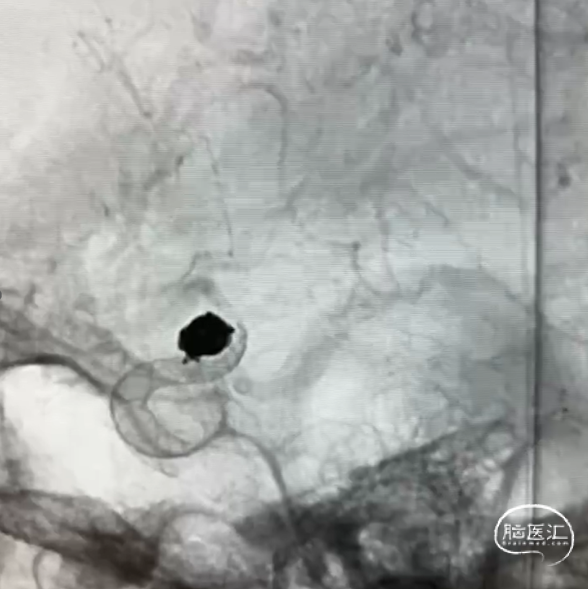

经栓塞微导管完全填入泰杰Perfiller®4mm*8cm-3D,再依次填入泰杰Perfiller®3mm*6cm-3D、Perfiller®2mm*4cm-3D、2枚Perfiller®1mm*2cm-3D。

造影显示动脉瘤达到完全致密栓塞,撤出栓塞微导管。